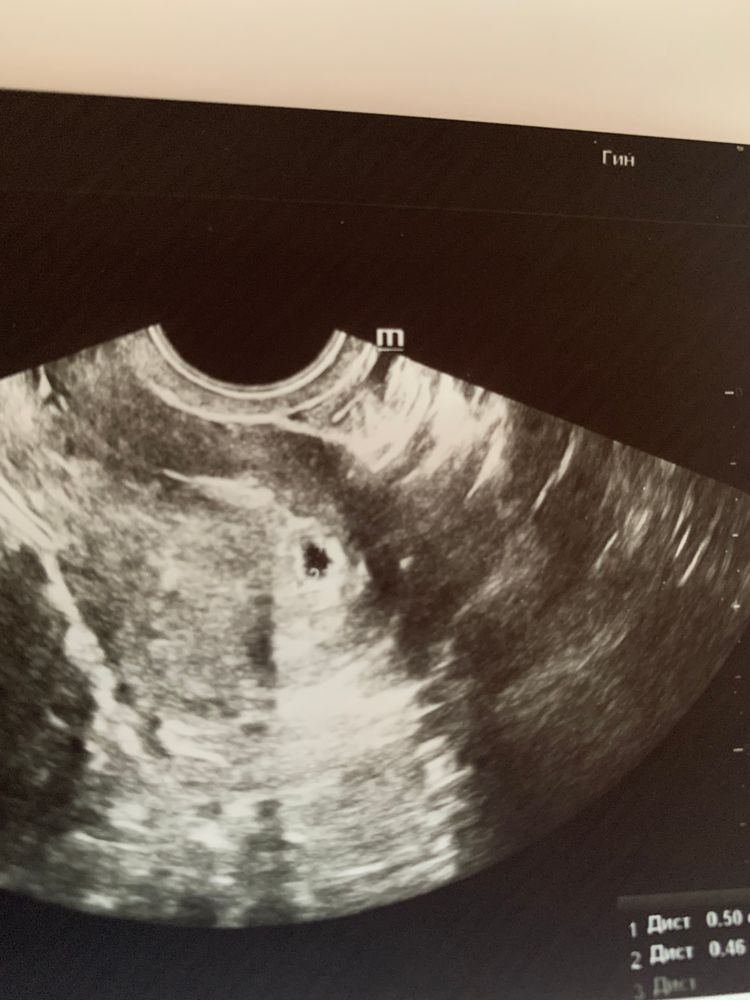

Девочки !! Скажите пожалуйста когда у вас увидели эмбриона ?

ИРА2010, Изображение Решила вторую беременность . Тут 5-6 недель

ИРА2010, Изображение Закорючка внизу пя это цифра 2.

А овуляция поздняя или обычная? Это играет большую роль. Но то, что не увидели ЖМ при ПЯ 13мм неочень хорошо. Вы главное в панику не впадайте, разные аппараты узи и по разному все показывают, верьте в малыша и меньше нервничайте, пусть сидит крепко бусинка 🙏🏻

Вот пришли результаты хгч 26.07- 31940 28.07-46216 Это нормально ?

ИРА2010, я смотрела ,где то пишут ,что мало ,на друг норма ! Еще читала ,что к 6-7 неделям хгч растет медленный . У меня уже голова кругом . Переживаю сильно и каждый день. Мажущие коричневые выделения (скудные ) уже больше недели … но нет боли никакой ,ничего не тянет